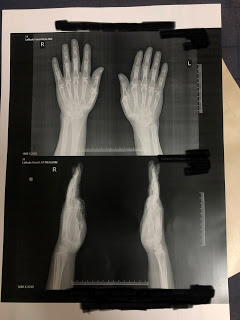

INVESTIGATIONS-

-Complete blood picture

-ESR

-CRP

-Rheumatoid factor

DIFFERENTIAL DIAGNOSIS-

1• Rhuematoid arthritis

2• Osteoarthritis